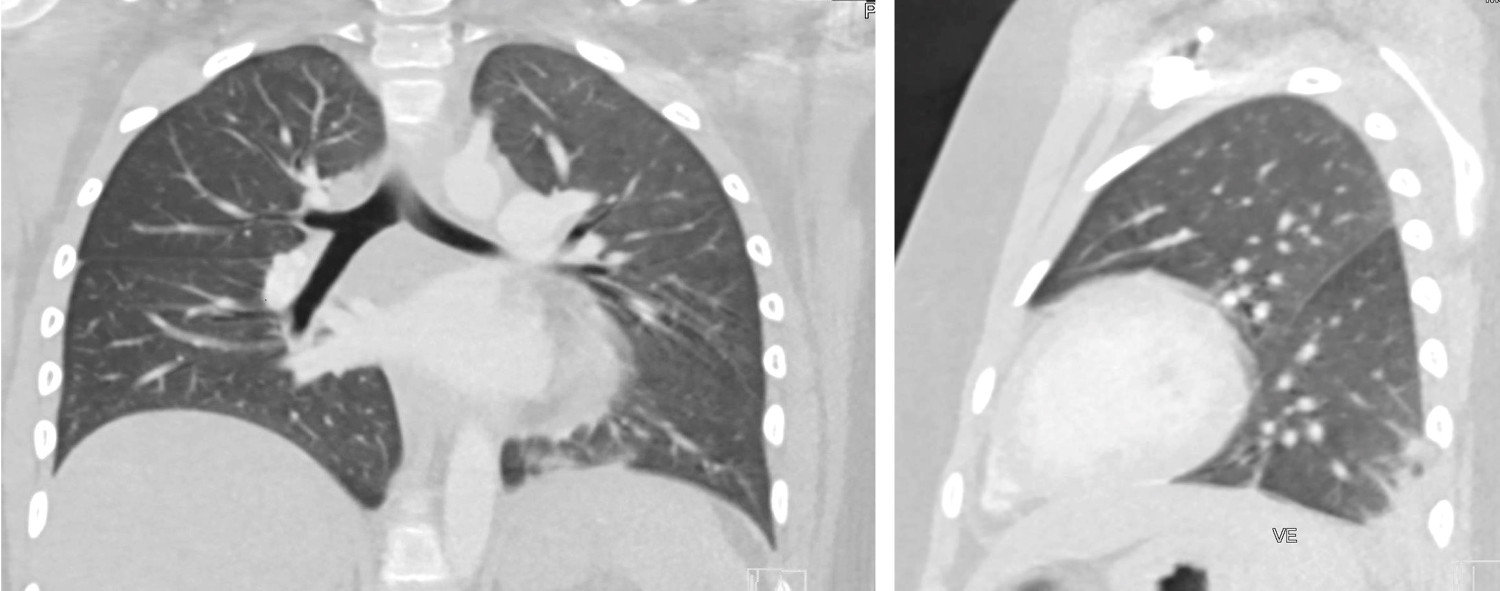

Pasienten pustet hele tiden selv, men med tidvis takypné og kortvarig behov for ekstra oksygen. CT thorax tatt dag 4, for å utelukke lungeembolisme, viste en basal fortetning og beskjedne mattglassfortetninger i venstre lunge, klar høyre lunge og ingen lungeemboluser (figur 2).